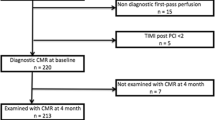

Study population

Among the 195 patients evaluated for study eligibility, 9 patients did not undergo CMR because of claustrophobia or refusal of the exam. Twenty-three patients were excluded after CMR because of time-to-reperfusion exceeded 12 h from symptoms onset, previous myocardial infarction / coronary revascularitation or insufficient LGE quality. One-hundred-sixty-three patients were finally included (Fig. 1). Patients were then divided according to Trevasc-CMR tertiles (Table 1). Fifty-three (32%) patients showed pre-PPCI blood flow in the ischemic myocardium at risk via the infarct-related artery (TIMI-flow-grade ≥ 2; n = 42) or collaterals (Rentrop-grade ≥ 2; n = 11). Patients in Tertile-3 tended to be older presenting with lower systolic blood pressure at hospital admission than patients in Tertile-1 or Tertile-2. Except for these variables, baseline characteristics were comparables across TRevasc-CMR tertiles (Table 2).

This study has several limitations. Firstly, it was conducted in a tertiary referral center for PPCI and CMR. Accordingly, we cannot exclude a referral bias. Trevasc-CMR tertiles showed an even distribution of clinical and hemodynamic factors influencing I/R damage [11]. However, our study design cannot completely remove bias in allocating subjects to the 3 tertiles. Ideally, this limitation can be overcome by repeating CMR at fixed time points in large cohort of patients. However, this type of study entails complex protocols arising also ethical concerns due to repeated administration of gadolinium-based contrast agent for IS. To the best of our knowledge the largest study serially repeating contrast-enhanced CMR in the early post-STEMI included only 30 patients [5]. We did not use T2*-mapping for IMH identification and quantification to obviate to off-resonance artifacts which are particularly cumbersome at interface between myocardium and lung [25].